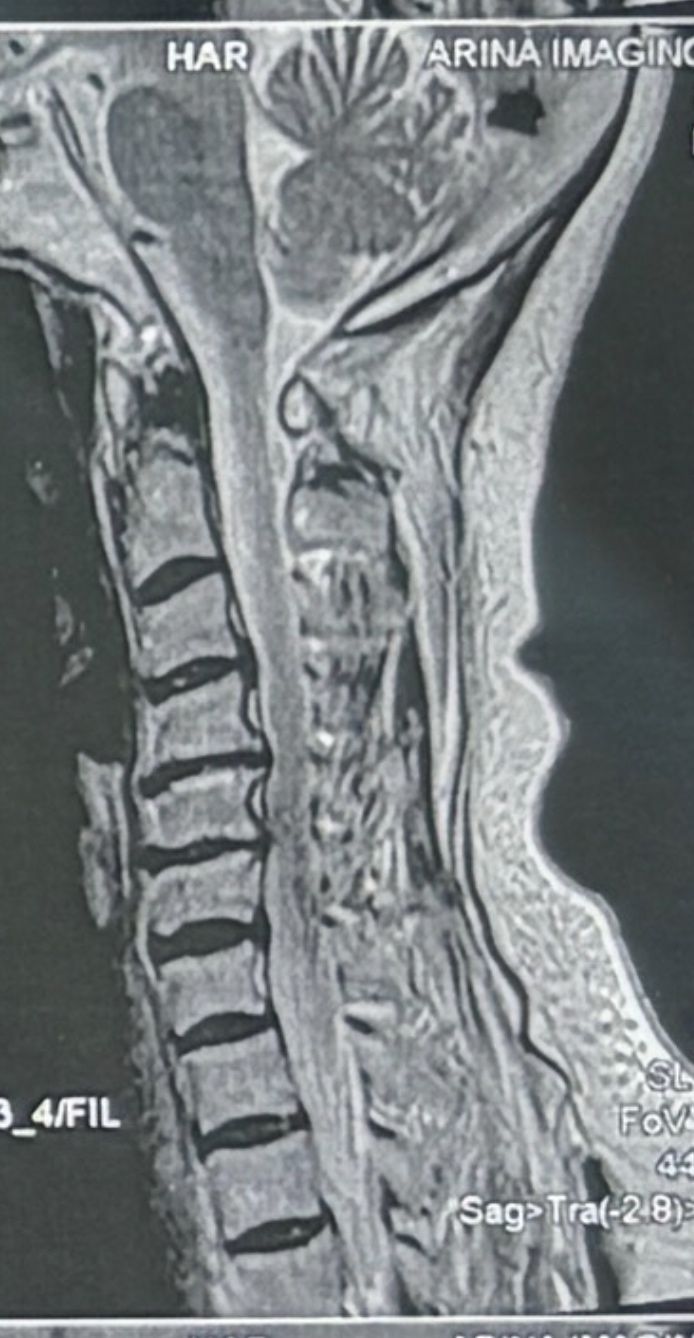

A 64-year-old male patient was referred to my clinic by a well-known neurosurgeon (Oct 2025) for evaluation and management of right-sided sciatic pain. The onset followed an incident in which his 18-year-old grandson accidentally pulled his leg. Relevant medical documents were reviewed and attached. He just has controled DM

On presentation, the patient denied any cervical pain. Nevertheless, as part of my routine examination protocol, a comprehensive cervical assessment was performed, including chiropractic, orthopedic, and neurological evaluations. Cervical range of motion was markedly restricted, and chiropractic motion and static palpations revealed hypertrophic pillar segments and multiple severe Facets restrictions .There were no upper motor neuron (UMN) signs at all noted during the examination.

Investigations and Management;

A cervical and thoracic MRI was requested, and lumbar treatment was initiated for his sciatic symptoms. The patient was also advised to follow up with his neurosurgeon regarding the cervical findings.in his mri a large hydronephrosis was noticed and For his large hydronephrosis he was asked to see a nephrologist ( he mentioned he had ESWL for kidney stone few years ago)

Upon further discussion with the patient after reviewing his cervical MRI with him , the patient mentioned that he had previously fallen from a three-story building, sustaining ankle fractures at that time.after seeing his cervical mri the possibility of C4,5, and possibly retrolisthesis of C5 was considered and CT scan from C/S and dynamic cervical x ray was requested

Discussion

Although the patient was asymptomatic from a cervical standpoint, MRI findings demonstrated cervical cord severe compression and possible mild edema and early myelomalacia. Based on these findings, I believe that cervical decompression surgery should be considered.

While some neurologists and chiropractors may defer intervention in the absence of overt clinical symptoms, in this case, early surgical decompression appears justified. Waiting for neurological deficits—such as gait imbalance, coordination difficulties, or gastrointestinal/genitourinary dysfunction—may result in irreversible spinal cord injury, as these deficits often persist even after surgical decompression.

Considering the patient’s age and progressive degenerative changes, including degenerative disc disease (DDD) and degenerative joint disease (DJD), delaying surgery could further increase the risks associated with operative morbidity and mortality. Keep in mind all kind of manipulation on his neck is absolutely contraindicated

Conclusion;

Early identification and management of clinically silent cervical cord compression with MRI evidence with or without myelomalacia may prevent irreversible neurological deterioration in future.on the other hand he has to take care of his kidney seriously

I welcome interprofessional opinions and discussion regarding the optimal management strategy for this patient’s cervical spine pathology, particularly concerning the timing and indications for surgical decompression in the absence of overt cervical symptoms.